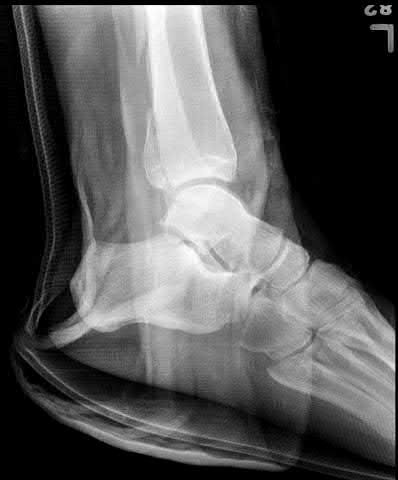

A 25-year-old female is involved in a motor vehicle collision. She presents with the isolated injury seen in Figures A through D. Her leg is swollen but her skin is intact. She has no clinical signs of compartment syndrome. Which of the following treatment options will allow for maintenance of fracture alignment and minimize the risk of soft tissue complications?

The patient presents with a closed distal third metaphyseal-diaphyseal distal tibia fracture with simple intra-articular extension. Immediate intramedullary nailing along with percutaneous fixation of the articular component provides appropriate restoration of length, rotation and alignment and minimizes the risk of wound complication.

Displaced distal third tibia fractures may be associated with simple intraarticular extension. Operative treatment of intra-articular distal tibia fractures has historically been performed with open reduction and internal fixation. Early open reduction and plate fixation of pilon fractures has been associated with high rates of infection and wound complication. In select patterns with simple articular extension, percutaneous screw fixation and medullary nailing may provide appropriate reduction with minimal soft-tissue risk.

Figures A and B demonstrate a distal third tibial shaft fracture with simple intra-articular extension. The axial and coronal CT cuts in Figures C and D further clarify the articular injury. Illustrations A and B demonstrate a comminuted distal third tibial fracture with simple intra-articular extension. Illustrations C and D are fluoroscopic images of the same injury after intramedullary nailing and percutaneous fixation of the articular component.